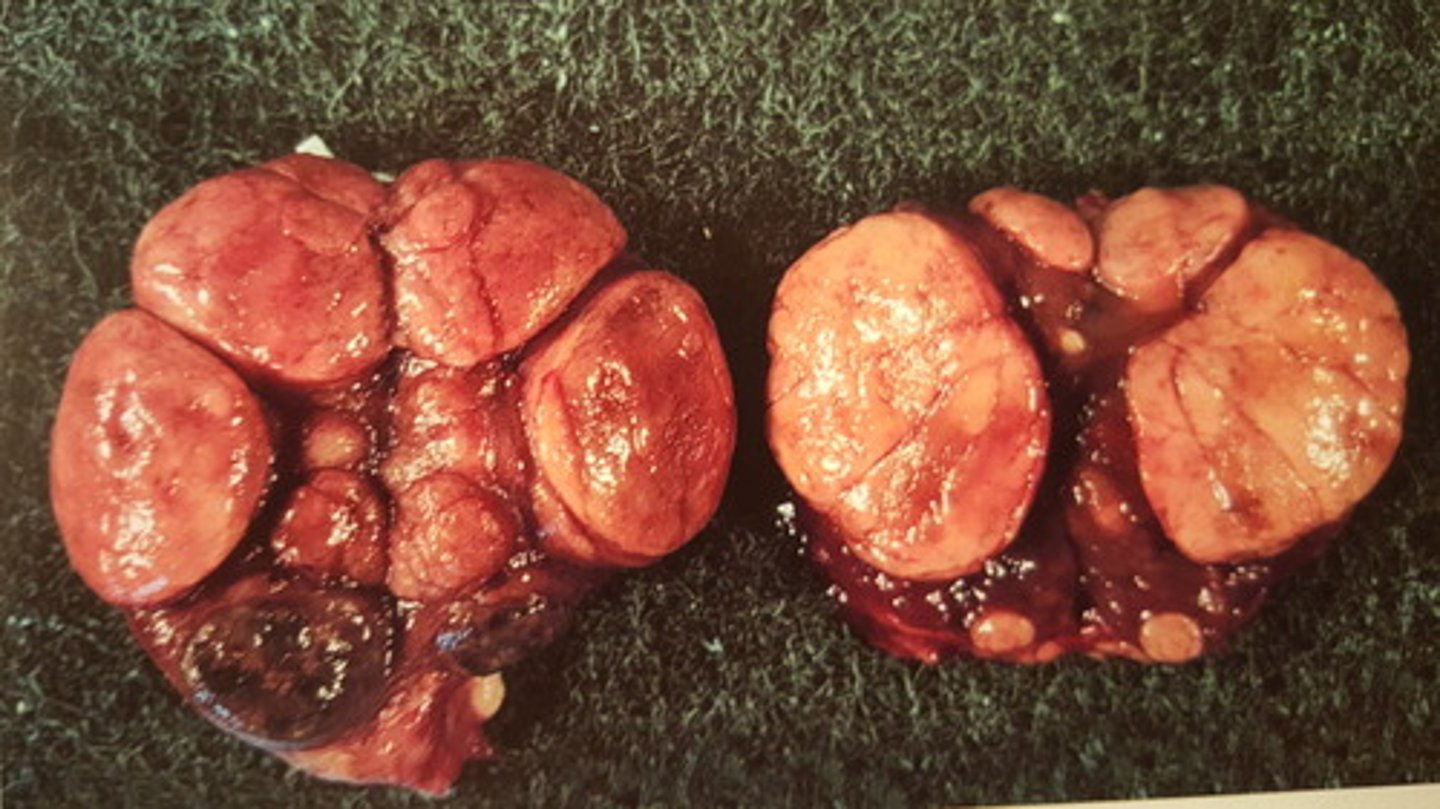

Akut multifokal massiv lever nekrose

Lever fra okse, hvad er den patoanatomiske diagnose?